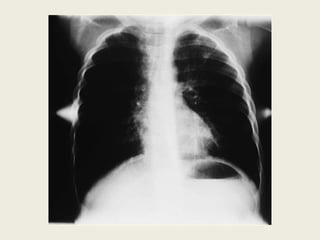

Radiologic Findings

Chest radiograph

• Normal

• Hyperinflation

– Increased anteroposterior diameter

– Translucent (dark) lung fields

– Depressed or flattened diaphragm